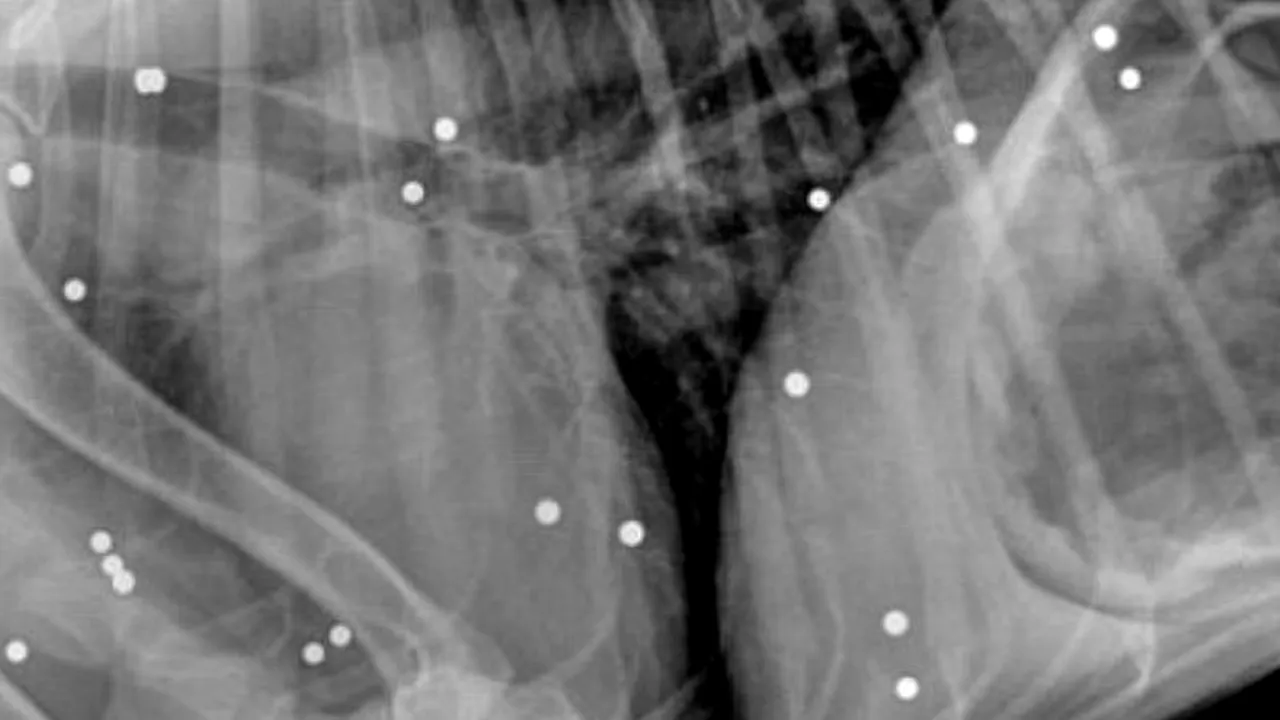

Un labrador a fost găsit agonizând în Waldoboro, Maine (SUA), în urmă cu câteva săptămâni. Câinele a fost dus de urgență la spital, iar medicii au fost uluiți când, după radiografie, au descoperit că fusese împușcat de peste 100 de ori cu un pistol cu aer comprimat, transmite Daily Mail.

Dr. Dean Domeyer, care a tratat-o pe Lady, a spus că cele mai multe alice erau în pielea animalului, dar a trebuit să le înlăture pe toate ca să prevină infecția.